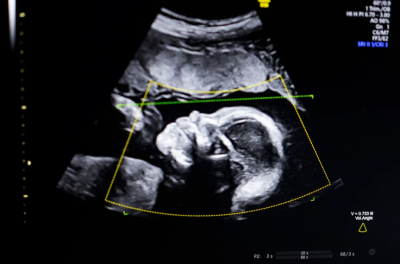

އަލްޓްރާސައުންޑުން ކުއްޖާގެ އައިބުތައް ދެނެގަންނަން ދުނިޔޭގައި ފުރަތަމަ އުފެއްދި އޭއައި ސޮފްޓްވެއާއަށް އެމެރިކާގެ ފުޑް އެންޑް ޑްރަގް އެޑްމިނިސްޓްރޭޝަން (އެފްޑީއޭ)ގެ ހުއްދަ ލިބިއްޖެއެވެ.

ބުސްތާމީ ވިދާޅުވި ގޮތުގައި މި ޓެކްނޮލޮޖީ ބޭނުންކުރަނީ "ކޮމްޕިއުޓަރު ވިޜަން އޭއައި" އެވެ. މީގެ އެހީގައި އަލްޓްރާސައުންޑްގެ ފެންވަރު ބެލުމާއި، ކުއްޖާގެ ގުނަވަންތައް ފުރިހަމައަށް ހުރިތޯ ބެލުމުގެ އިތުރުން، އޮޓޮމެޓިކުން ރިޕޯޓްތައް ތައްޔާރުކޮށްދީ ކްލިނިކަލް މަސައްކަތްތައް ފަސޭހަކޮށްދެއެވެ.

މި ސޮފްޓްވެއާ ތަމުރީނުކުރުމަށް އެތައް ލައްކަ އަލްޓްރާސައުންޑް ތަސްވީރުތަކެއް ބޭނުންކޮށްފައިވެއެވެ. ބުސްތާމީ ވިދާޅުވީ، އެންމެ އުނދަގޫވި ކަމަކީ ހަމައެކަނި އޭއައި މޮޑެލް ބިނާކުރުން ނޫން ކަމަށާއި ނަމަވެސް ތަފާތު އެކި ނަސްލުތަކުގެ މީހުންނަށް މި ޓެކްނޮލޮޖީ އެއްވަރަކަށް މަސައްކަތްކުރާކަން ކަށަވަރުކުރުން ކަމަށެވެ.